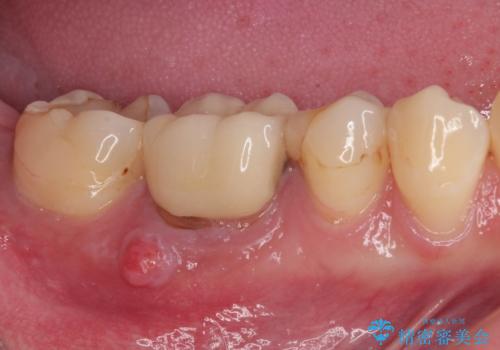

- 以前処置をした歯の歯肉からの出血するとのことで来院された患者様です。

以前むし歯治療をした後から定期的に痛むことがあるとのことで、レントゲン写真より神経組織が失活していることが予想されました。

銀歯を外すと神経組織の一部が取り除かれており、歯根に付け根に穴が空けられている状態でした。

出血の原因は以前の治療で空けられた穴であると考え、封鎖をするとともに根管治療を行い、その後オールセラミッククラウンにて補綴治療を行うこととしました。